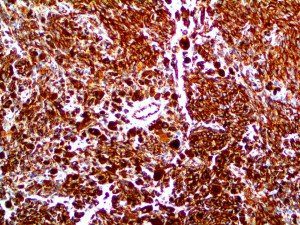

It is the ICU physician who is most likely to witness one of the deadliest manifestations of the abnormal immunological response, the cytokine storm syndrome (CSS). This response is also referred to by some as the cytokine release syndrome (CRS). CSS is characterized by continuous activation and expansion of macrophage and lymphocyte populations, which secrete large amounts of cytokines, causing the cytokine storm. This massive cytokine release is akin to hemophagocytic lymphohistiocytosis (HLH) disease, a syndrome characterized by initial unchecked and persistent activation of cytotoxic T lymphocytes and NK cells.

Clinical and laboratory manifestations of HLH include fever, enlarged liver and/or spleen, neurologic dysfunction, coagulopathy, liver dysfunction, cytopenias (i.e., low levels of erythrocytes, leukocytes, and/or platelets), hypertriglyceridemia, hyperferritinemia, hemophagocytosis, and eventually diminished NK cell activity as the immune system becomes progressively paralyzed. HLH can be familial (primary HLH) or secondary to another disease process (sHLH), such as rheumatic disease, in which it is referred to as macrophage activation syndrome (MAS, characterized by elevated ferritin).

This activation induces inflammatory monocytes to highly express IL-6, starting a localized and then systemic cascade effect that results in hyperproduction of IL-6, which accelerates the inflammatory process. Because IL-6 also increases vascular permeability, excessive levels cause blood vessels to become very leaky. This, along with clotting factors released from vascular endothelial cells, stimulates the coagulation cascade, resulting in microthrombosis (tiny clots), which leads to ischemia and tissue death of the kidney, intestines, heart, liver, brain and extremities.